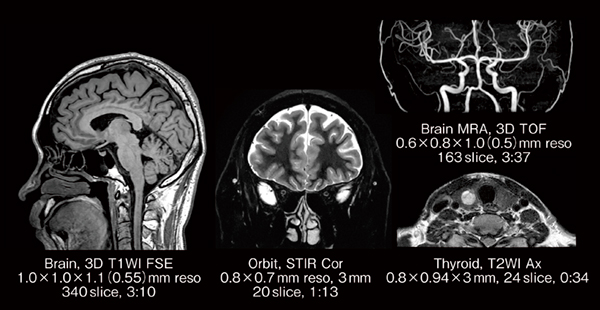

富士フイルムヘルスケアは,MRIシステムの新しいモデルとして,70cmの開口径を持つワイドボア1.5T*1超電導型MRIシステム「ECHELON Synergy(エシェロン シナジー)」*2(図1)を2023年3月27日に発売し,4月14日〜16日にパシフィコ横浜 (神奈川県横浜市) で開催された「2023国際医用画像総合展(ITEM 2023)」に出展しました。

ECHELON Synergyは,撮像時に断層画像の位置・角度の自動設定が可能な機能やノイズ除去技術など,人工知能(AI)技術*3を活用した機能・技術を搭載したMRIシステムで,検査ワークフローの効率化と検査時間の大幅な短縮が期待できます。本稿では,特徴的な3つの機能と,新しく臨床現場にご提案したい3つのアプリケーションについて解説します。